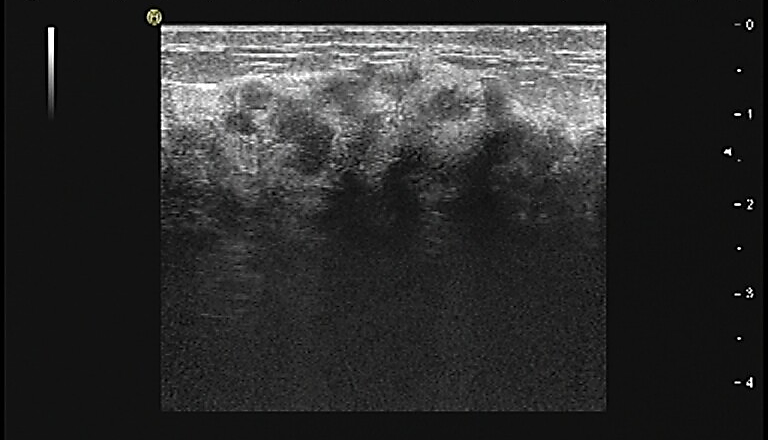

图5.新辅助治疗2周期后的乳腺彩超评估

图6新辅助治疗6周期后的乳腺彩超评估

患者自第3周期新辅助治疗起,正处于3~6月间上海新冠疫情封控时期,对影像学评估造成了较大的影响。根据ESMO新冠期间乳腺癌诊治临床处理优先原则,对于HER2+乳腺癌的新辅助/辅助治疗作为优先实施治疗,而对于新辅助治疗临床缓解的患者的影像学评估可以适当延后。因此,对于该患者4个周期后的影像学评估没有实施。

患者在完成6周期新辅助治疗后,由于出现中度血小板降低、Ⅱ度粒缺,给予对症支持治疗、推迟根治性手术,3周后继续完成1个周期的HP双靶治疗(汉曲优6mg/kg+帕妥珠单抗420mg)。整个新辅助治疗期间复查心超LVEF>62%。

新辅助治疗6周期后再次CT评估,提示两肺未见明显异常密度影。纵隔内未见确切肿大淋巴结。双乳腺体致密,左乳局部可见点状高密度影,未见确切异常强化灶;双侧腋窝未见明显肿大淋巴结(图9)。

图9.新辅助治疗6周期后胸部CT平扫(箭头处提示金属clip位置)

临床疗效评估为PR。